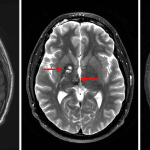

- 2 x 1 cm lesion centered in the right globus pallidus and 1.5 x 1 cm lesion in the right midbrain, both of which have internal T1 and T2 signal hyperintensity, peripheral T2 signal hypointensity, and blooming signal hypointensity on susceptibility weighted imaging, indicating a peripheral hemosiderin ring

- Additional small focus of susceptibility artifact in the dorsolateral right thalamus

- The midbrain lesion exerts mild mass effect on the cerebral aqueduct without evidence of hydrocephalus

- Developmental venous anomaly in the right thalamus, posterior limb of the right internal capsule, and posterior right lentiform nucleus draining into a right lateral tentorial sinus

- Cerebral cavernous malformations (cavernomas)

Cerebral cavernous malformations (cavernomas) centered in the right globus pallidus and right midbrain, both of which have internal T1 and T2 signal hyperintensity suggesting subacute hemorrhage. No significant surrounding edema. The midbrain lesion exerts mild mass effect on the cerebral aqueduct without evidence of hydrocephalus. Associated developmental venous anomaly draining into a right lateral tentorial sinus.

Additional small focus of susceptibility artifact in the dorsolateral right thalamus, which could represent an additional tiny cavernoma versus sequela of prior microhemorrhage.